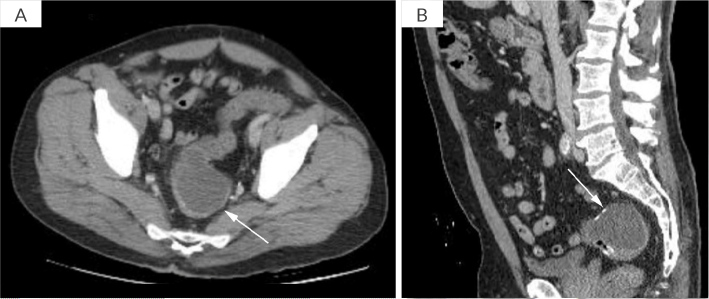

结直肠黏液囊肿是一种罕见的发生在胃肠道的黏液囊肿,对诊断和治疗提出了挑战。我们报告了首例使用腔内金属支架(LAMS)成功治疗腔外结直肠黏液囊肿的病例。65岁男性,既往有憩室炎病史,行部分结肠切除术后出现便秘和腰痛。计算机断层扫描(CT)显示直肠吻合口附近有一个5.4厘米的囊性结构。超声内镜(EUS)发现上皮下病变呈“洋葱皮”状,吸痰细胞学证实为结肠-结肠粘液囊肿。处理包括eus引导放置8 × 8 mm LAMS,允许引流,冲洗和吸痰腔。在2年的随访期间,完全解决,无复发。本病例证明了先进的内镜技术,特别是LAMS在治疗腔外结直肠粘液囊肿方面的潜力。虽然需要进一步的研究来比较LAMS与其他治疗方式的疗效,但该程序为某些患者提供了手术的微创替代方案。学习要点:一种治疗罕见的结肠黏液囊肿的新方法,使用顺腔金属支架。

Colorectal mucoceles are rare mucinous cysts arising in the gastrointestinal tract and presenting diagnostic and therapeutic challenges. We report the first successful treatment of an extraluminal colorectal mucocele using a lumen-apposing metal stent (LAMS). A 65-year-old male with a known medical history of diverticulitis treated with a partial colectomy presented with constipation and low back pain. Computed tomography scan (CT) revealed a 5.4 cm cystic structure adjacent to the rectal anastomosis. Endoscopic ultrasound (EUS) found a subepithelial lesion with an "onion peel" appearance, and aspiration cytology confirmed a colo-colonic mucocele. Management consisted of EUS-guided placement of an 8 × 8 mm LAMS, allowing for drainage, irrigation, and suctioning of the cavity. Complete resolution was achieved without recurrence over a 2-year follow-up period. This case demonstrates the potential of advanced endoscopic techniques, particularly LAMS, in managing extraluminal colorectal mucoceles. While further research is needed to compare the efficacy of LAMS with other treatment modalities, this procedure offers a minimally invasive alternative to surgery for certain patients.